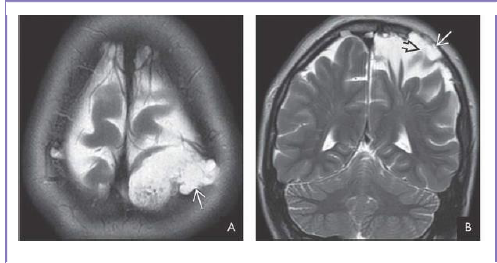

What is shown?

Coronal T2WI shows the intradiploic CSF collection with

encephalomalacic brain stretched and tethered into the lesion . Classic “growing” skull fracture

(leptomeningeal cyst).